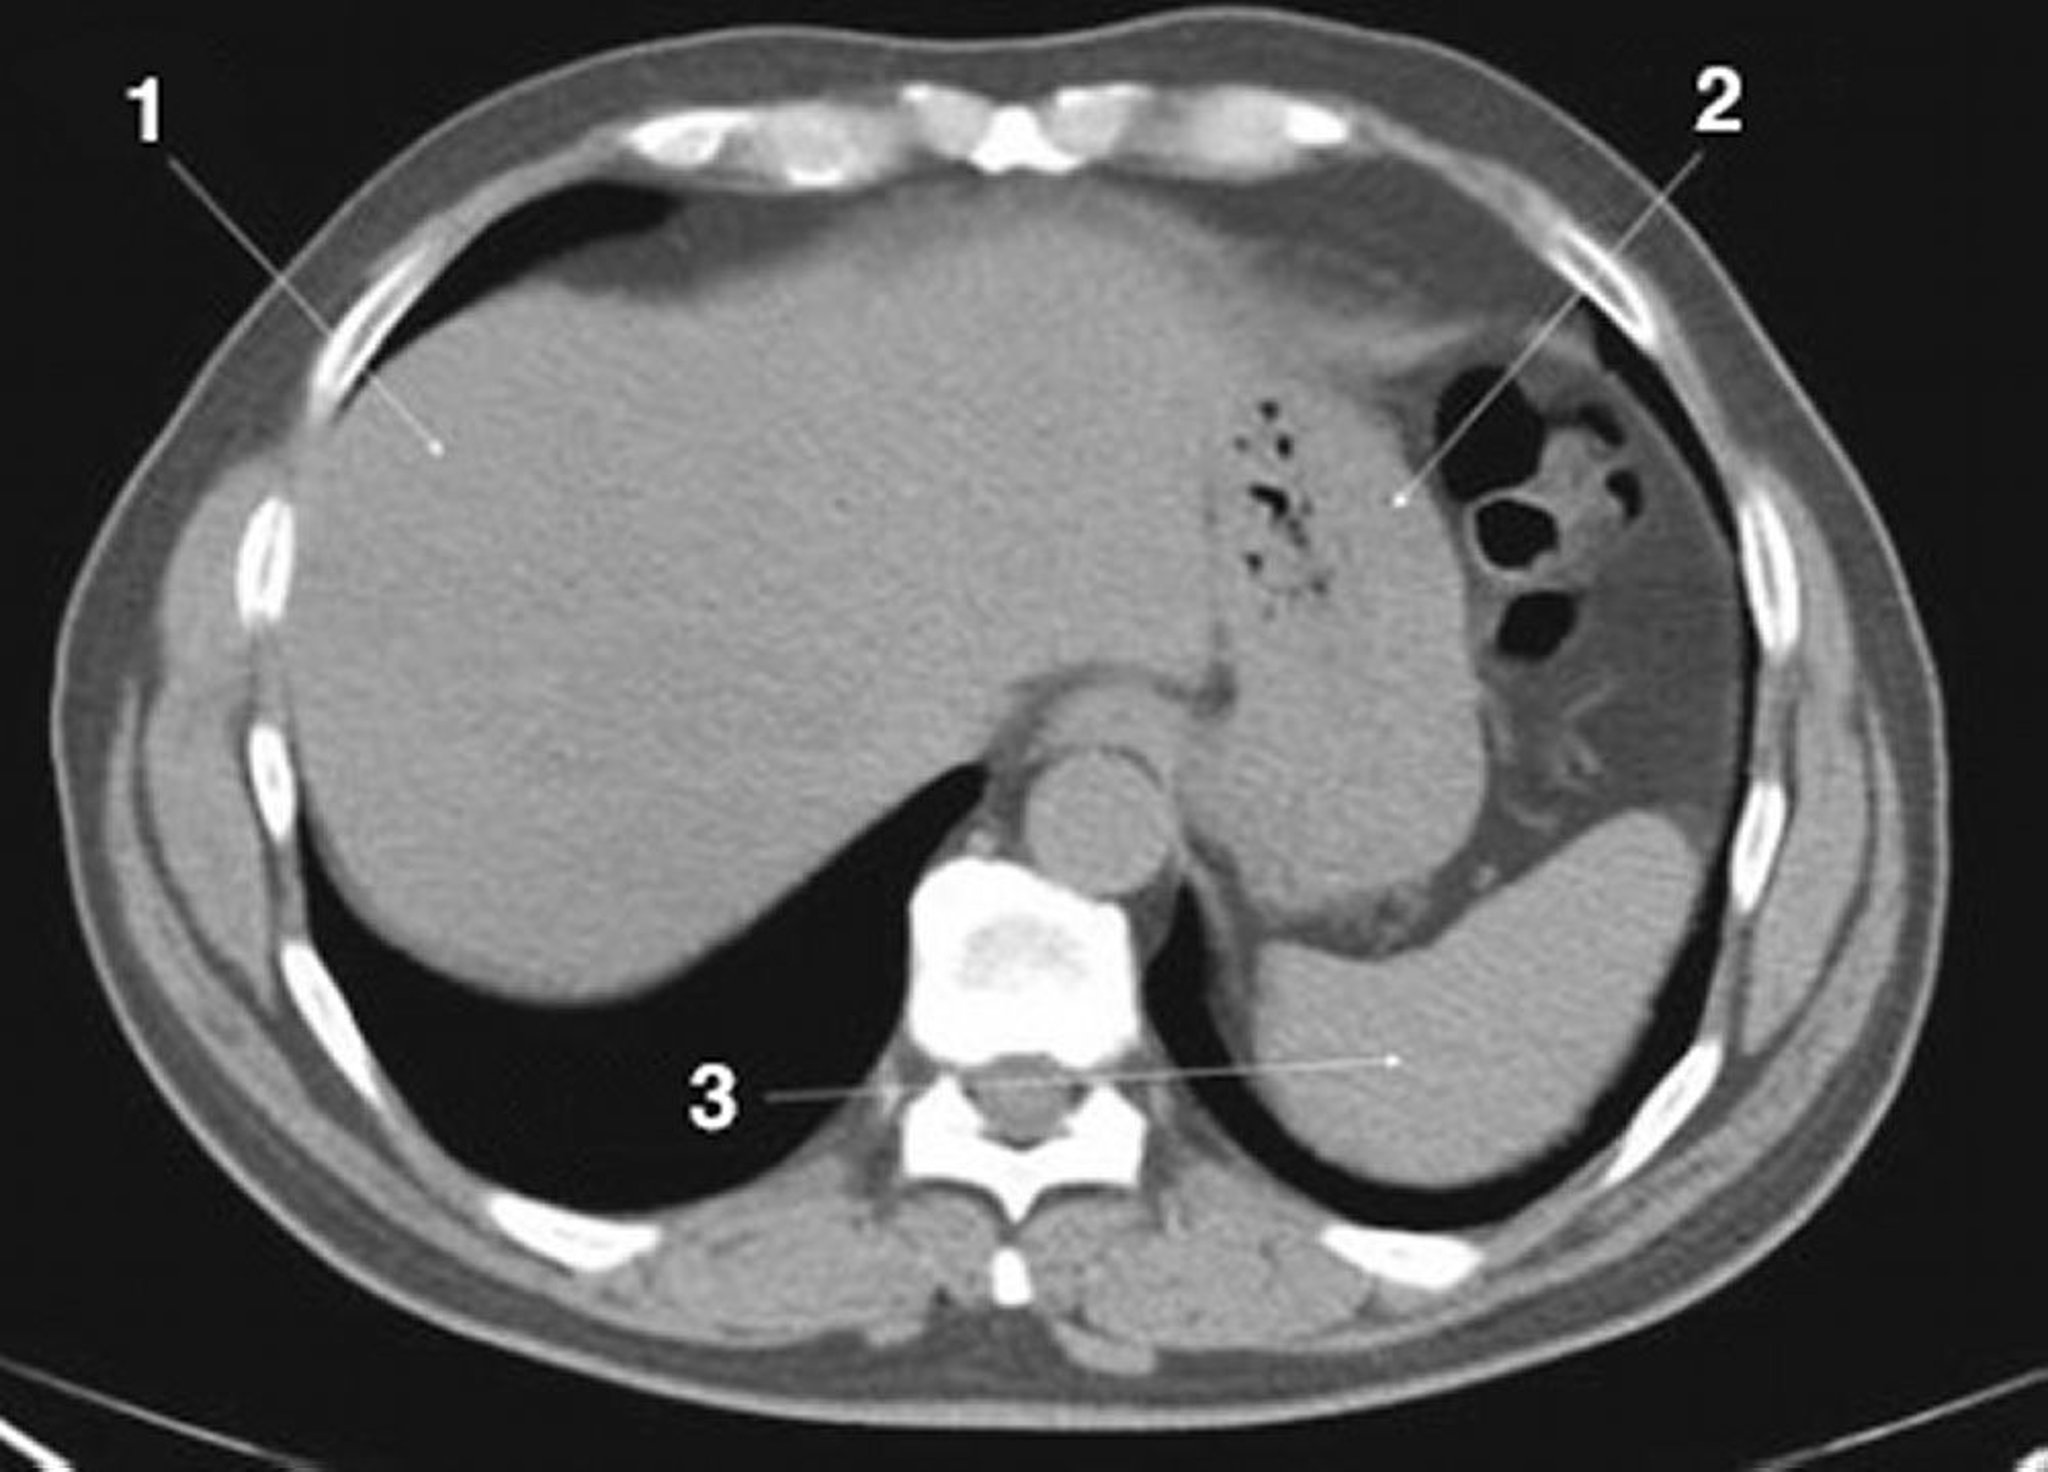

CT-Scan von Abdomen und Becken mit normaler Anatomie ohne Kontrastmittel (Folie 3)

1 = Leber; 2 = Magen; 3 = Milz.